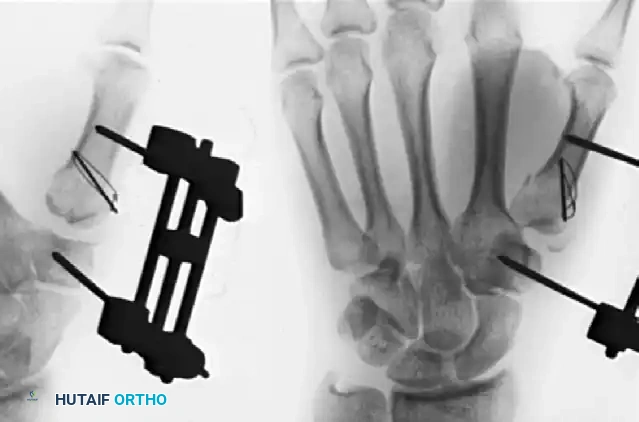

Alternative Techniques: External Fixation and Tension Band Wiring

In cases of severe comminution (complex Rolando fractures) where the articular fragments are too small or numerous to accept 2.7-mm screws, rigid internal plating may be impossible. In these scenarios, the principles of ligamentotaxis must be employed.

The Distractor Technique

For highly unstable, comminuted fractures, an external fixation distractor combined with limited internal fixation (such as tension band wiring or fine K-wires) is a highly effective salvage technique.

1. Pin Placement: Place two threaded half-pins into the trapezium (or radius, depending on the frame design) and two into the distal thumb metacarpal shaft.

2. Distraction: Apply the external fixator and distract the joint. Ligamentotaxis will pull the comminuted fragments toward their anatomic positions via their capsular and ligamentous attachments.

3. Limited Internal Fixation: If large enough fragments exist, use a tension band wiring construct or percutaneous K-wires to secure the major articular pieces while the ex-fix unloads the joint.

🔪 Surgical Technique 67-4: Severe Rolando Fracture Management

As demonstrated in Figure 67-15, a severely comminuted Rolando fracture can be successfully treated by an external fixation distractor combined with tension band wiring. Because the fracture is inherently unstable, the distractor is left in place for a full 8 weeks. This prolonged neutralization protects the articular cartilage during healing, frequently resulting in excellent carpometacarpal and metacarpophalangeal function.